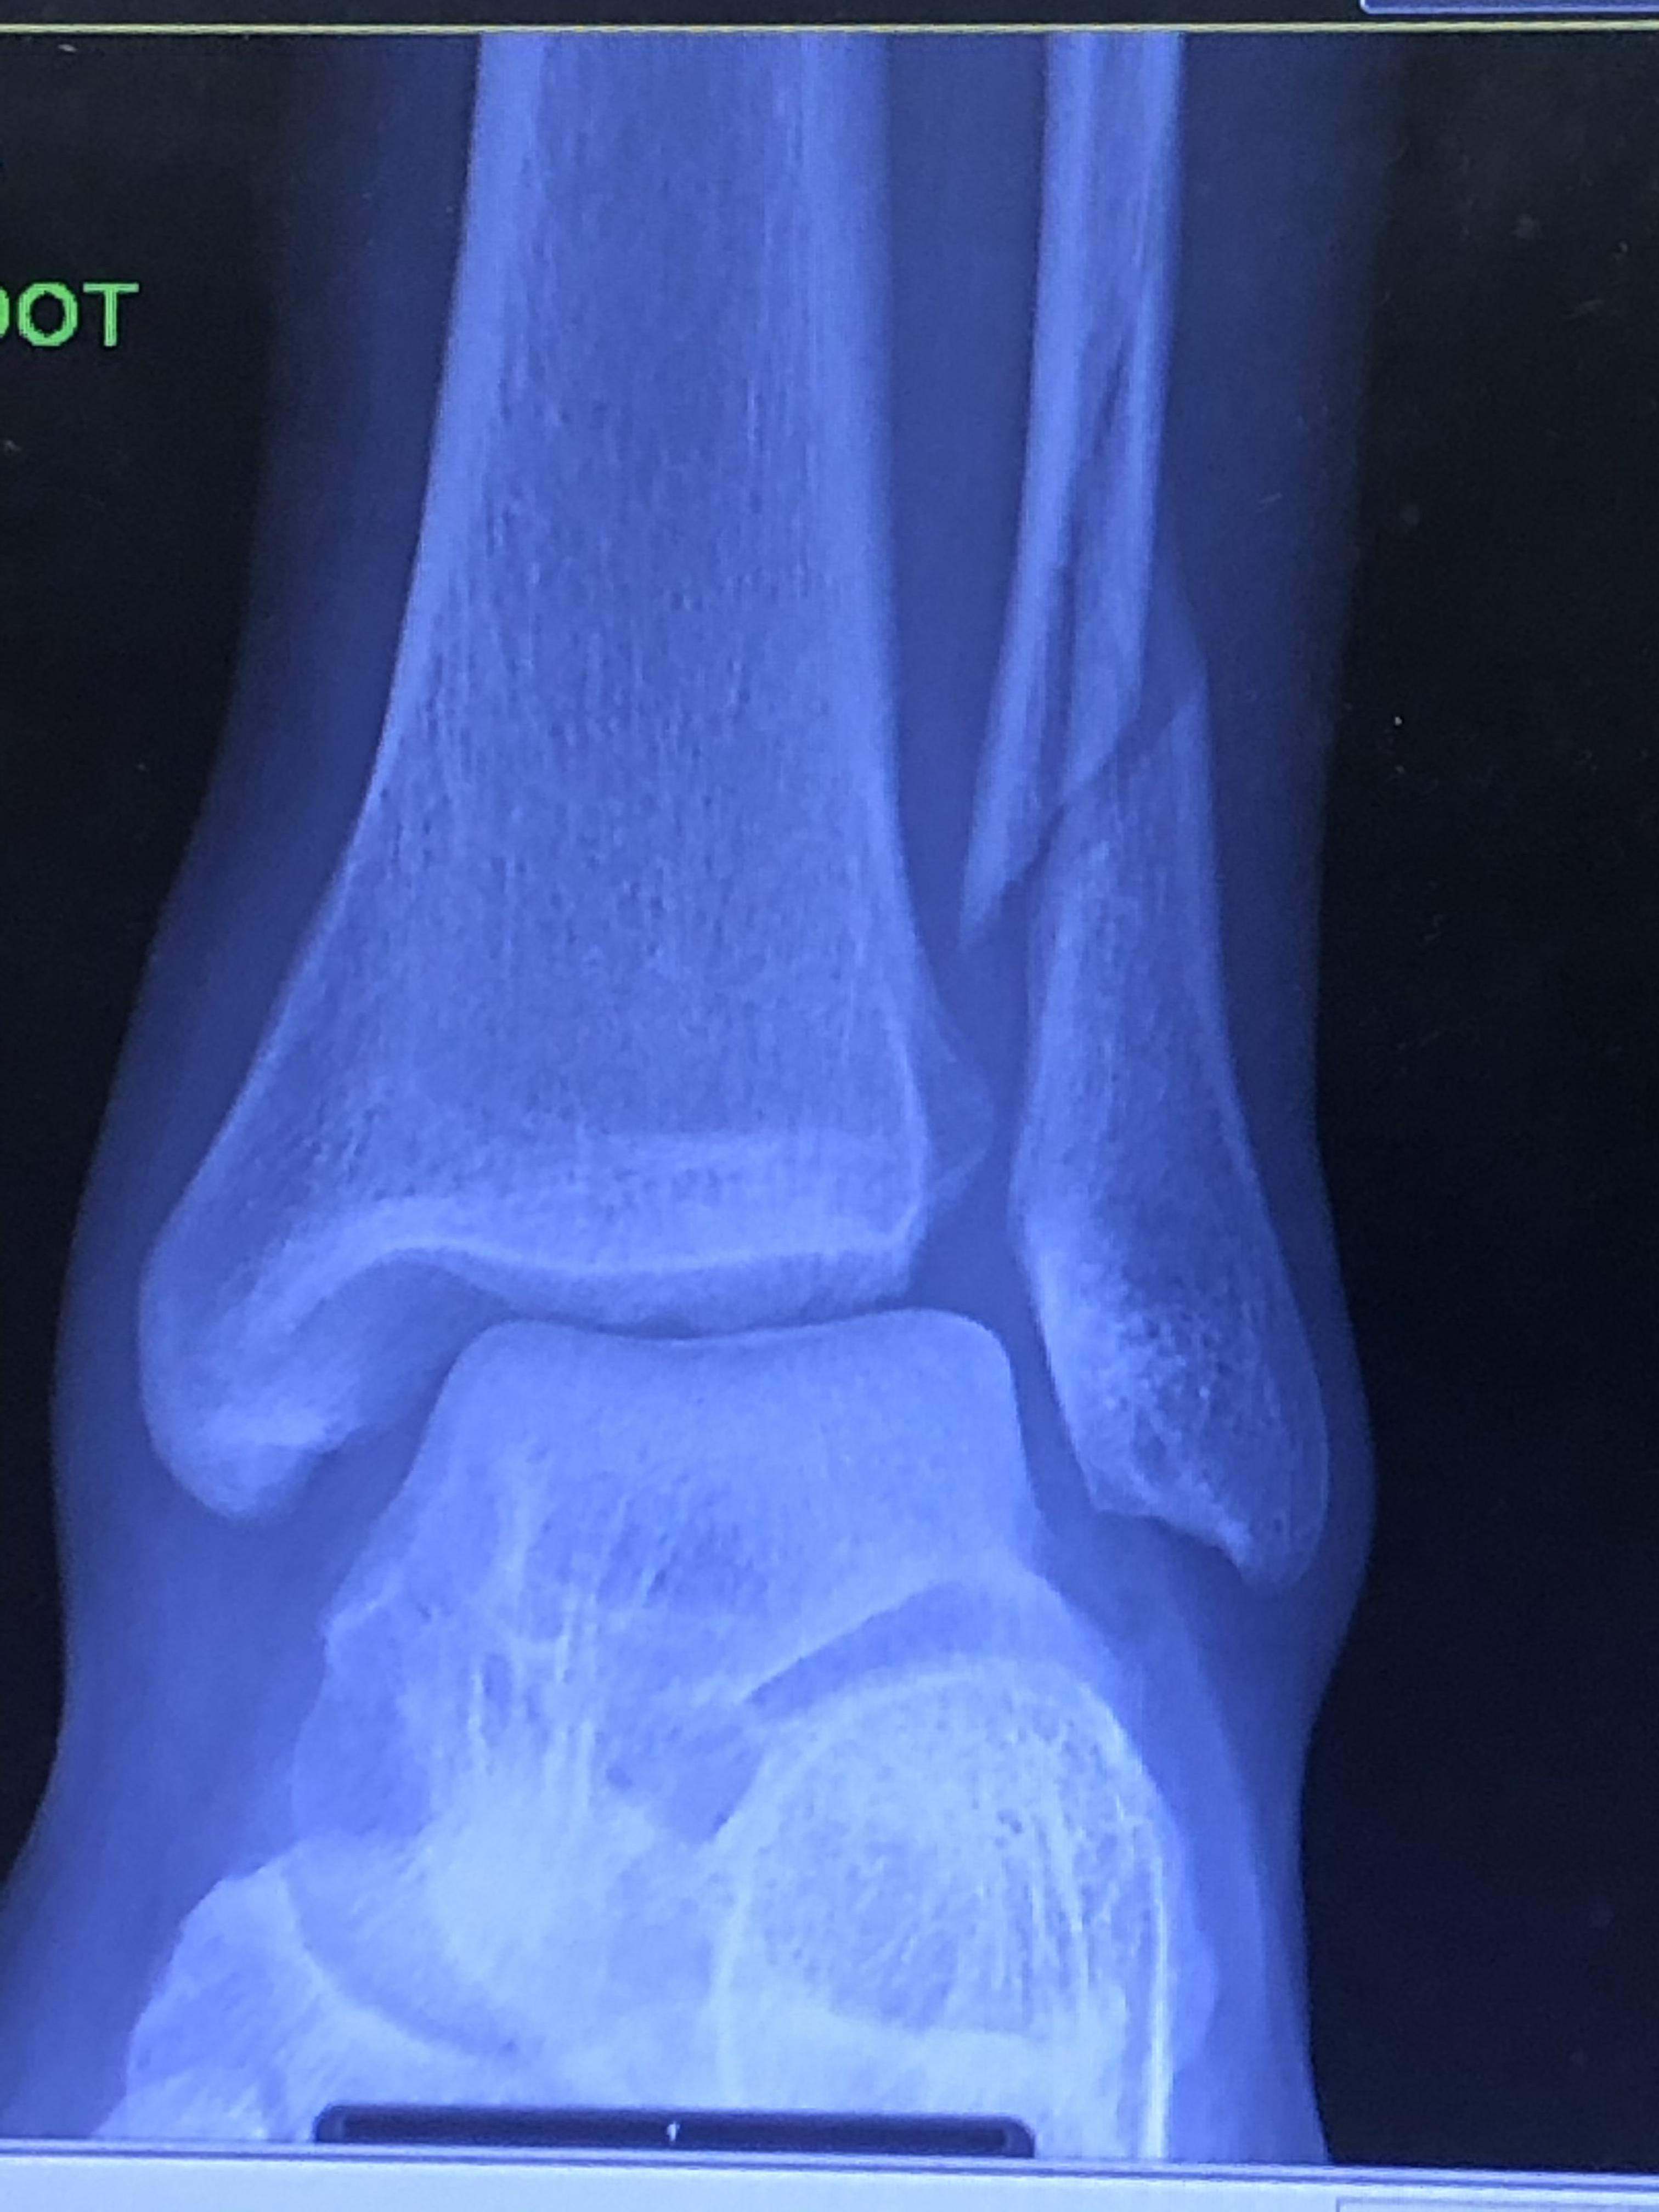

Fractured Foot, Xray Photograph by Science Photo Library Pixels Broken Bones Football A metatarsal fracture refers to a break or fracture in one of the long bones (metatarsals) located in the foot. This article reviews the current evidence on traumatic fractures in soccer, and assesses how this can guide practice. Within the foot, the 5th metatarsal (located in the arch) is a commonly fractured bone and. The bones in the ankle, foot. Broken Bones Football.